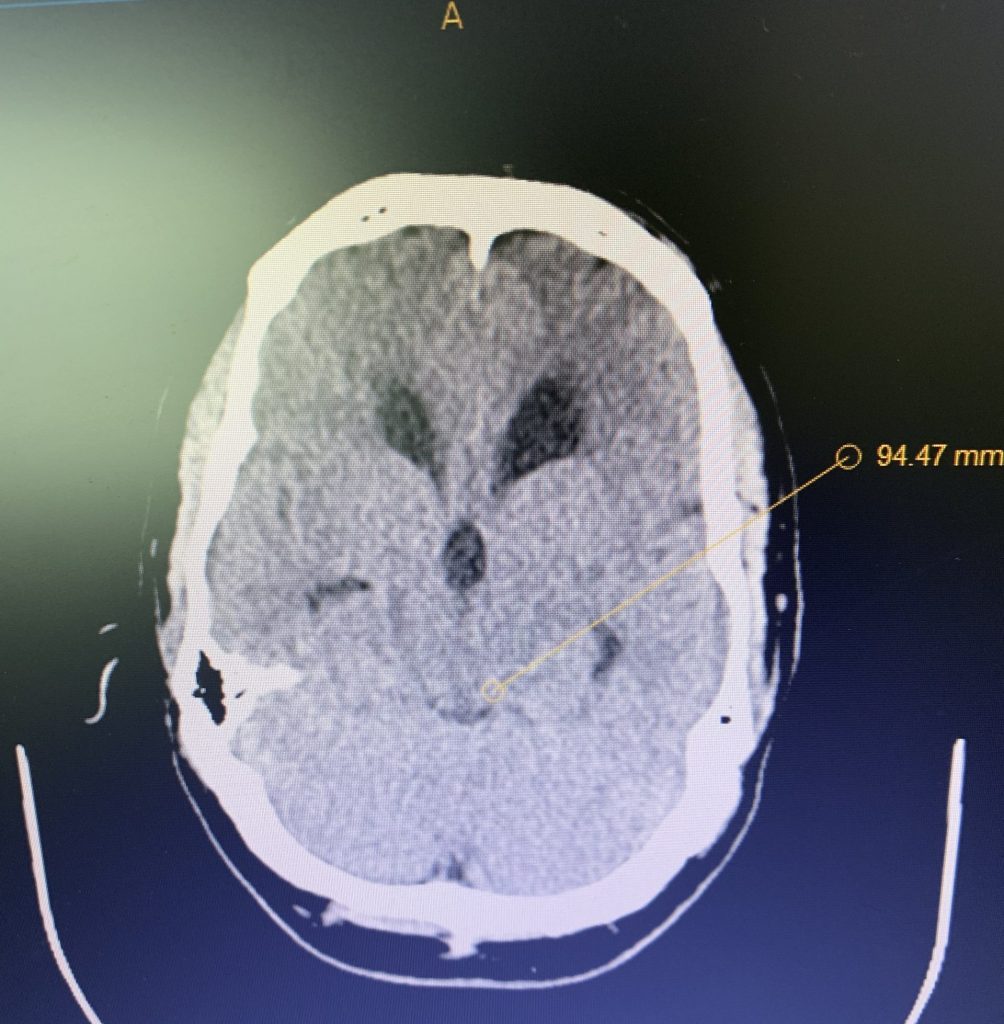

On initial examination, the patient was neurologically intact without complaints of headache. His imaging; however, did show hydrocephalus, most notably the lateral and third ventricles with a normal sized fourth ventricle. Given that the patient had no complaints, a decision was made to follow this expectantly and he was referred for a neuro-ophthalmologic evaluation, which confirmed no evidence of papilledema. MRI was otherwise negative.

Several weeks later, the patient re-presented to the office complaining of significant headaches and gait disturbance and a decision was made at that point to recommend shunting.

Figure 1B,C: Pre-operative CT images.

Prior to shunting, a head CT was obtained and the head CT in addition to documenting a patten of obstructive hydrocephalus suggested a possible mass lesion compressing the aqueduct at its inferior aspect. Figure #1 demonstrates the hydrocephalus and the possible lesion. A decision was made at this point that the patient had obstructive hydrocephalus that was now symptomatic and he was taken for a laparoscopic-assisted ventriculoperitoneal shunt.